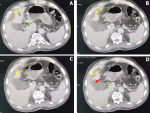

Abdominal imaging: it showed gallbladder with a transverse diameter of 42 mm, a sludge and a calculus embedded in the cystic duct measuring 5 mm with parietal thickening at body level on the hepatic side, 7 mm thick at most, which is the site of a parietal defect communicating with a subcapsular fluid collection opposite segments IV and V, 23 mm thick at most and extending over approximately 75 mm. Densification of peri-vesicular and sub-hepatic fat (Figure 1).

Figure 1: (A, B, C, D) abdominal CT finding on admission: axial sections